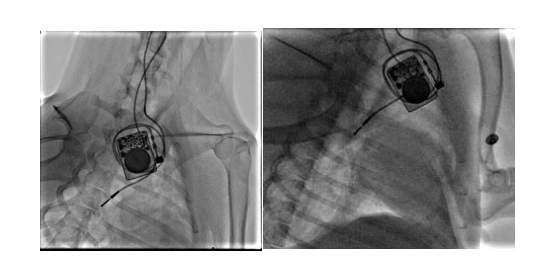

团队构建犬的慢性房颤动物模型,分析无创体表心电标测和有创心外膜心电标测系统采集的心电信号的相关性。我们顺利获得经颈静脉介入(图10)和右外侧开胸小切口(图11)两种方法建立快速起搏右心房的犬慢性房颤模型

9 经颈静脉介入路径构建右心房快速起博犬的慢性房颤模型

10 经右侧胸部小切口构建右心房快速起搏犬的慢性房颤模型